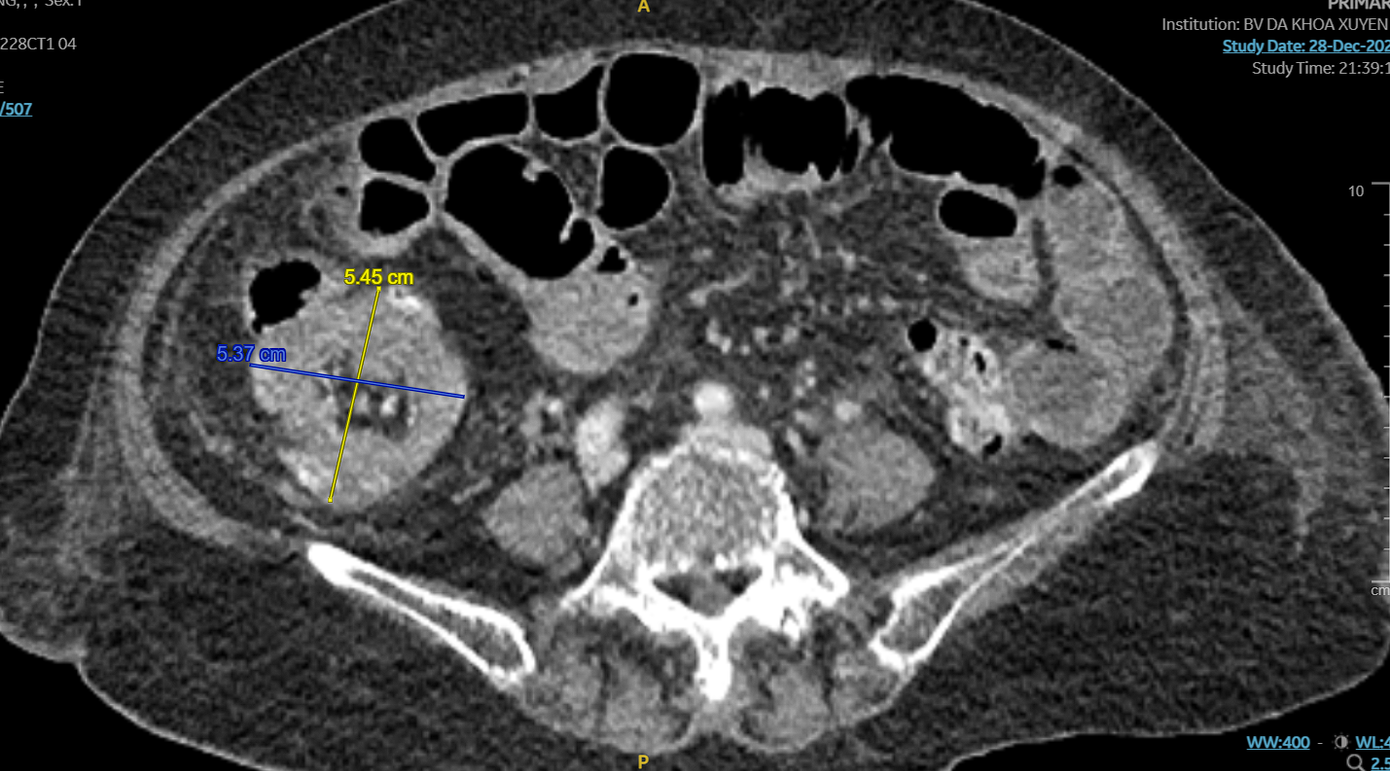

| Hình ảnh CT cho thấy vị trí bất thường trong ổ bụng của người bệnh |

Bệnh nhân được chỉ định chụp CT-Scanner bụng chậu phát hiện một khối lồng ruột non vào đại tràng tại góc hồi - manh tràng có kích thước lớn. Các bác sĩ chẩn đoán người bệnh bị lồng ruột hồi manh tràng do khối u manh tràng.